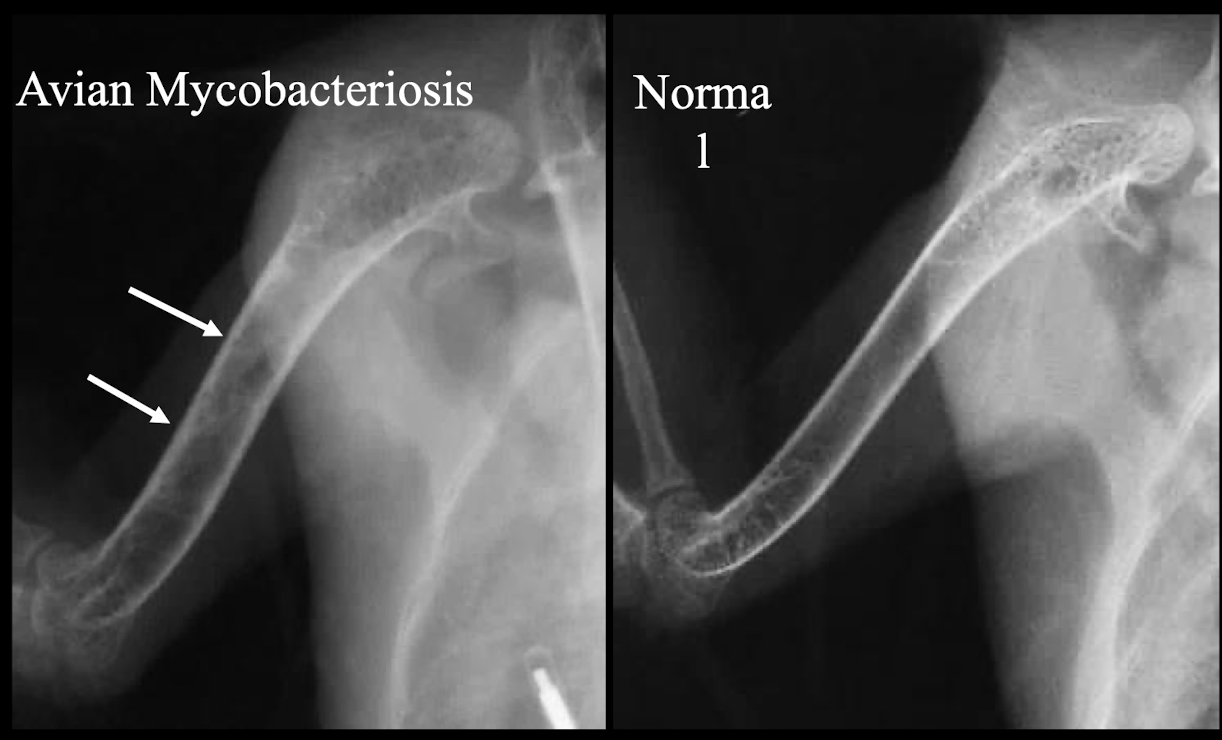

What two specific avian diseases can cause pathologic hyperostosis?

Avian Mycobacteriosis and Avian Leukosis.

What radiographic signs are indicative of Metabolic Bone Disease in birds?

Pathological fracture and poor bone density.